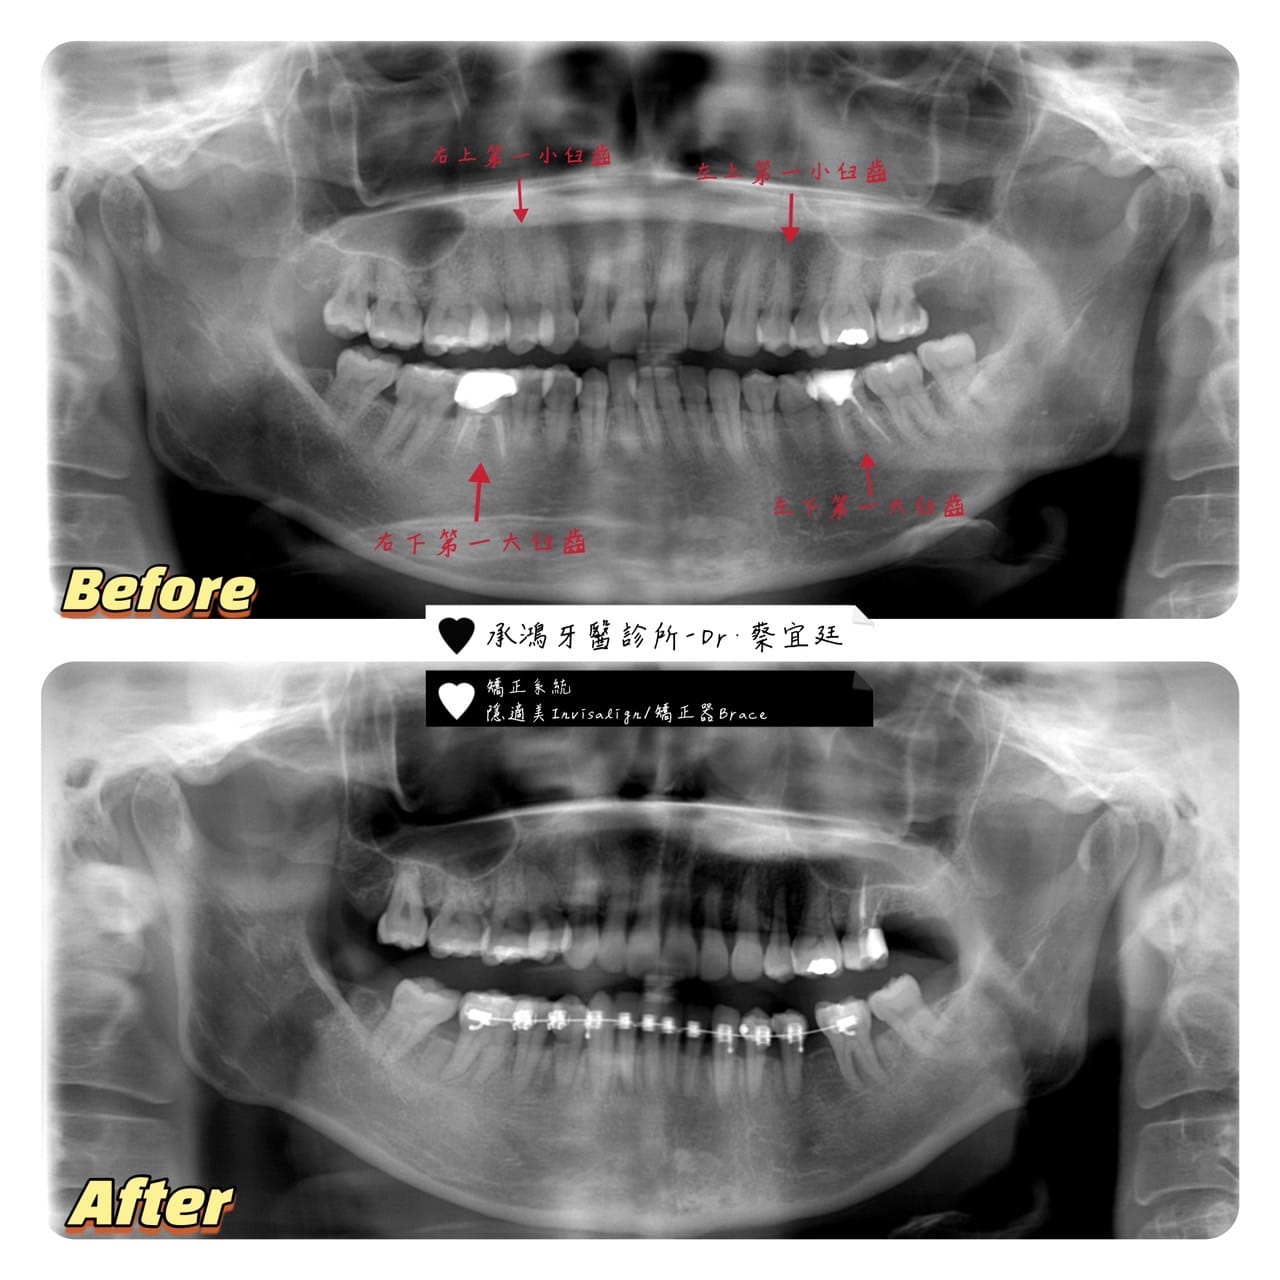

🔹🔹🔹矯正第⼀階段完成🔹🔹🔹

欸!蔡宜廷醫師 不是只做 #隱適美隱形矯正 嗎?為什麼這個患者的下排是 #⼤鋼牙 啊?🤔 🤔 🤔 🤔 🤔

因為這個患者在下顎的矯正治療計畫是⽤ #替代法的⽅式。#傳統矯正 Brace 系統有⼀個強項,在進⾏⽔平⽅向移動的進度會很快💨。替代法的療程,會需要關到比較⼤的空隙。這個時候就會先⽤ #傳統矯正系統把空隙關到差不多之後,再移除裝置,換成 #隱適美隱形矯正系統

⼀般⿒顎矯正都是以拔⼩⾅⿒為主,利⽤拔牙的空隙去把不整⿑的地⽅排列整⿑。這裡的替代法不是⼀般常規的拔除⼩⾅⿒,是拔除 #⼤⾅⿒

在這個患者的治療計畫裡,拔除了 #左側及右側下顎第⼀⼤⾅⿒。把後⾯的 #第⼆⼤⾅⿒及第三⼤⾅⿒ 往前移動 #去替代掉拔除第⼀⼤⾅⿒的空隙。

給 #矯正醫師 評估後,確定智⿒真的沒有可以利⽤的部分,這個時候再拔也不遲唷(當然有發炎的情況就例外了)。上排的部分就沒有特別難度

- 拔除右側上顎及左側上顎第⼀⼩⾅⿒